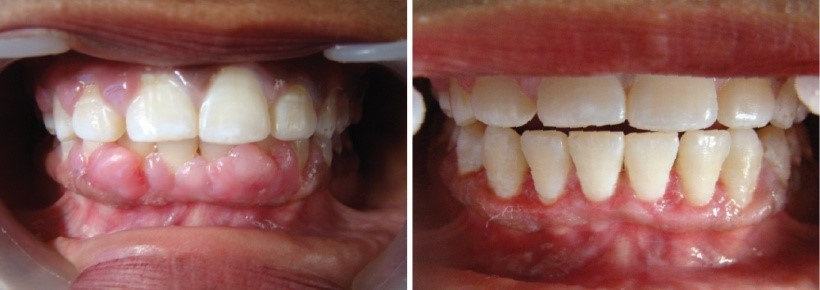

GINGIVECTONY & GINGIVOPLASTY

Gingivoplasty is a surgical procedure done to shape the gums by cutting off the excess gum tissue. This is also called gum contouring.

Gingivectomy is a surgical procedure used to treat swollen, diseased gums and get rid of pocket.